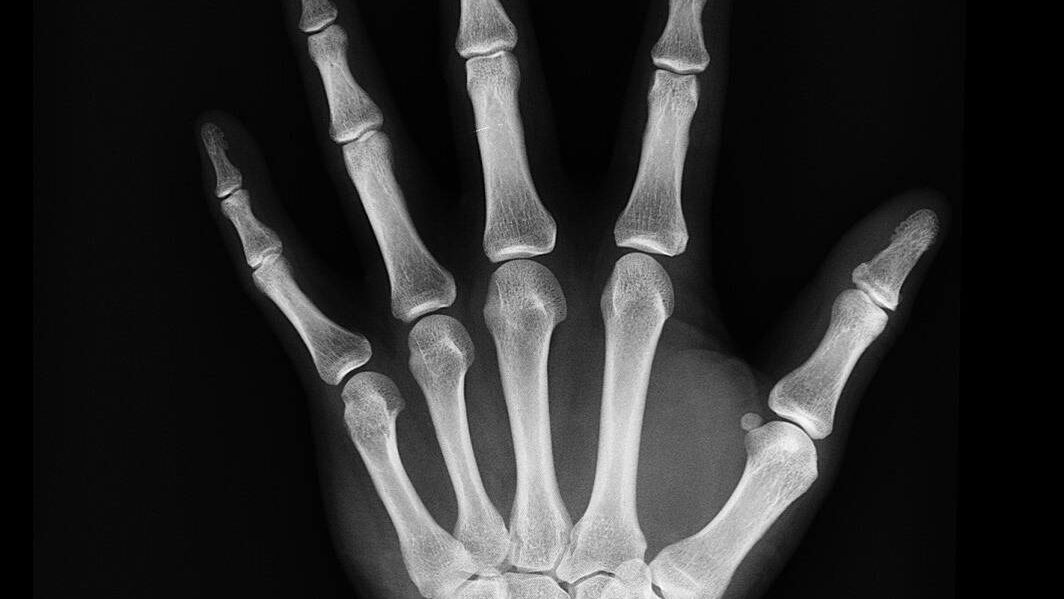

Quello a cui è arrivata M2Test è realizzare un sistema che, tramite tre mini radiografie a bassissimo dosaggio, riesce a valutare l'elasticità dell'osso. Il test può essere eseguito in maniera significativa anche sulla mano, a differenza di quanto accade nella densitometria classica, che va a valutare localmente i luoghi di frattura.

«Le tre mini radiografie prese a livello della mano non dominante sulle tre dita centrali vengono caricate sulla piattaforma di M2Test, dove un algoritmo proprietario le elabora e, in cinque minuti, restituisce un report in grado di validare il rischio di fratture. Sarà poi il dottore a refertare il tutto» continua Alessandra Nicolosi, CEO e co-founder di M2Test.

In pratica, il test permette di determinare la qualità della struttura trabecolare, analizzando la distribuzione dei carichi per mezzo di una strumentazione radiologica portatile “palmare” dedicata, che acquisisce l’immagine radiografica (proiezione A-P) delle epifisi prossimali di indice, medio ed anulare della mano non dominante e di un avanzato modello ingegneristico che valuta il modulo elastico apparente E* nella regione di interesse, indicativo della resistenza ossea.

I risultati delle simulazioni e l’entità dei toni di grigio dell’immagine vengono elaborati in un indice strutturale, BSI – Bone Structure Index, che è stato introdotto per evidenziare il contributo dell’organizzazione spaziale delle trabecole alla capacità di reggere i carichi, a prescindere dal livello locale di mineralizzazione.